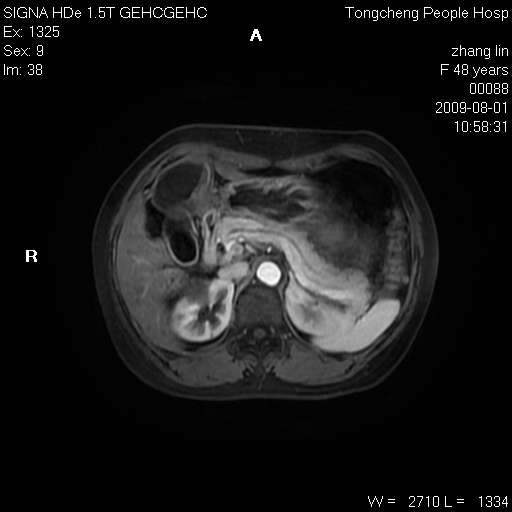

女,48岁。健康体检,彩超发现右肾占位性病变。平素健康。

临床诊断:右肾占位性病变,性质待定(囊肿?肿瘤?)。

上中腹部mr平扫+增强扫描,图像如下:

右肾上极见一类圆形病灶,t1wi呈等信号t2wi呈等高混杂信号,三期增强无强化,边界清---考虑囊肿出血。

同反相位均表现为等信号,病变无强化,考虑含蛋白的囊肿可能,弥散加权相或许有些帮助,

肝囊肿

慢性胆囊炎